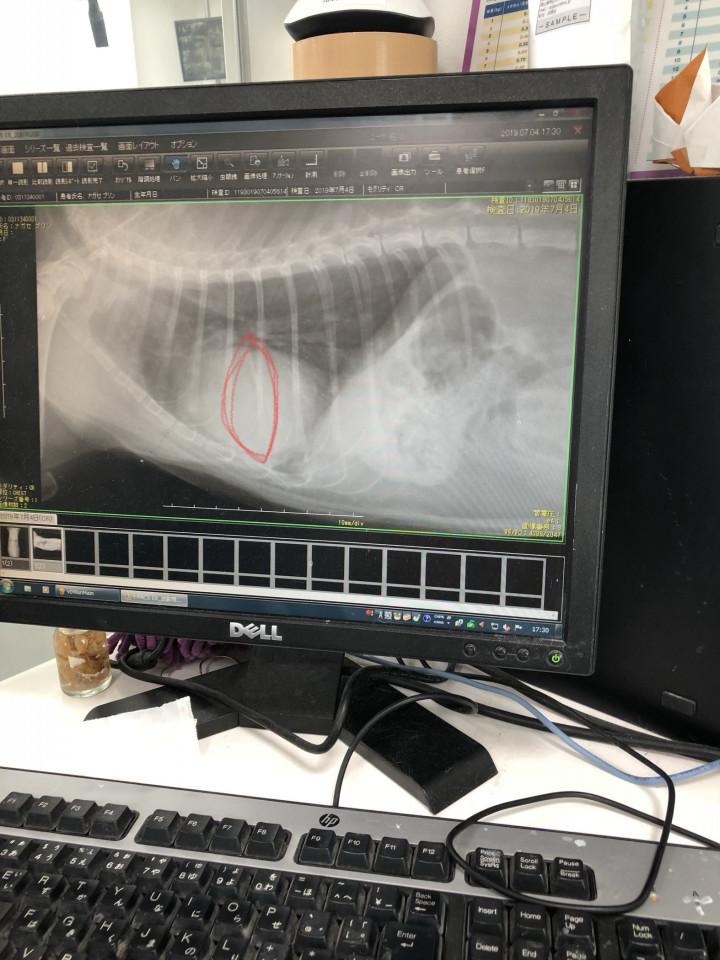

先生がエコーで見たけど

特に心配いらないみたい。

でもそんなに心配なら

レントゲン取ります?って

聞かれたから、お願いしますって言った。

待つことしばし……

呼ばれて診察室へ。

そこで言われたのはこうでした。

「落ち着いて聞いてくださいね。

本来、咳が出る原因を調べるために

レントゲンを取りました。

レントゲンでは肺に異常は

なかったんですよ。

ただ……

この子の心臓なんですが……

大きすぎなんです。

普通の子の2倍はあるでしょうか……

萎んだレモン位が

通常の心臓の大きさです。

かなり大きいですよね……」

※赤いのが通常の大きさらしい。

ぷりんのは明らかに大きい!

「恐らく、咳の原因は心臓です。